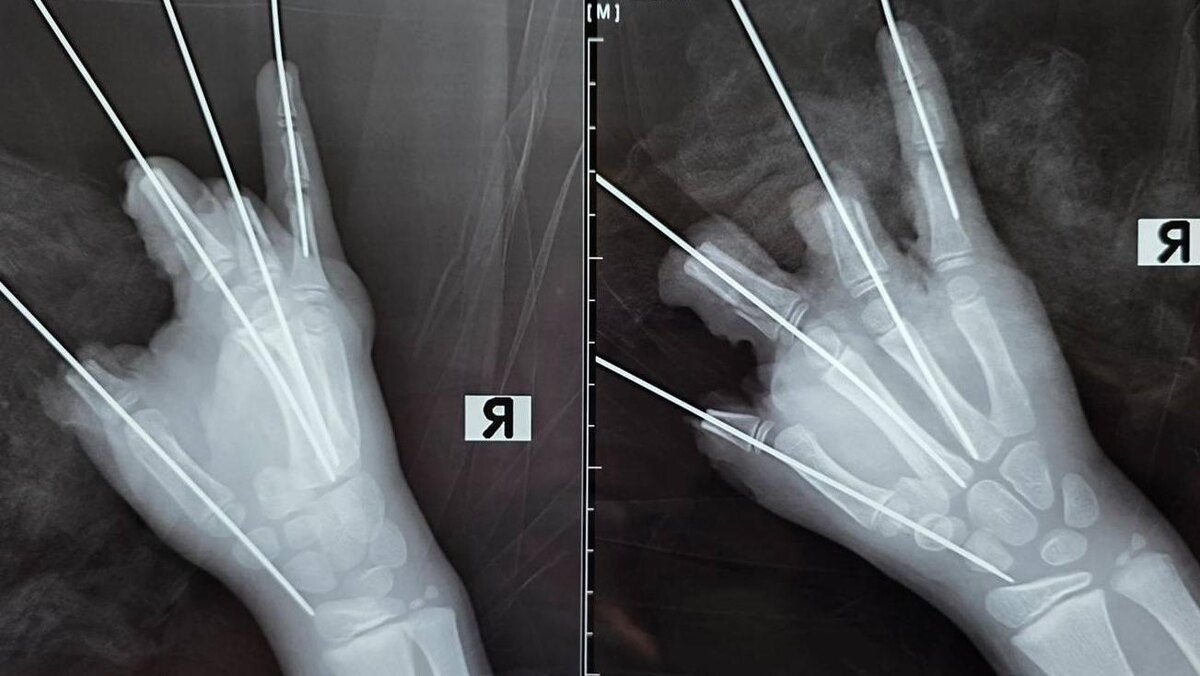

Сообщается, что взрыв привёл к травматической ампутации четырёх пальцев и к значительному повреждению мизинца. У пострадавшего диагностировали открытый перелом и вывих пястной кости. Также врачи констатировали размозжение и дефекты мягких тканей.

Врачи доставили мальчика в Педиатрический университет в 21:40, пострадавшего тут же поместили в операционную. Специалисты удалили свободно лежащие фрагменты костей, соединили отломки фаланг среднего и безымянного пальцев, а также удалили нежизнеспособные ткани и сформировали культи большого, среднего и безымянного пальцев.

Фото: gpmu.org